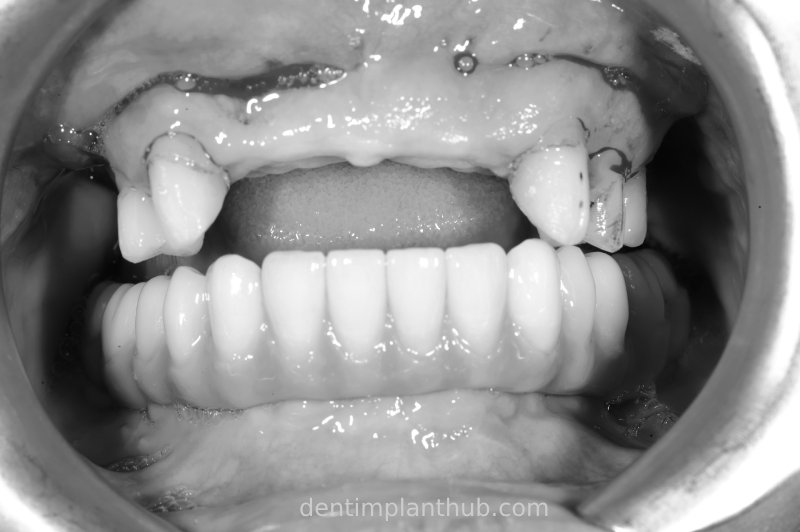

Intraoral photo of temporary crown after surgery on 11/10/23

7/6/24 Mandibular preparation for wearing a fixed prosthesis supported by a maroon bridge

Intraoral photographs after putting it on

Temporary crown photograph of the upper jaw on 7 June 24

Photo of temporary crown worn into the mouth on the day of surgery, 7 June '24